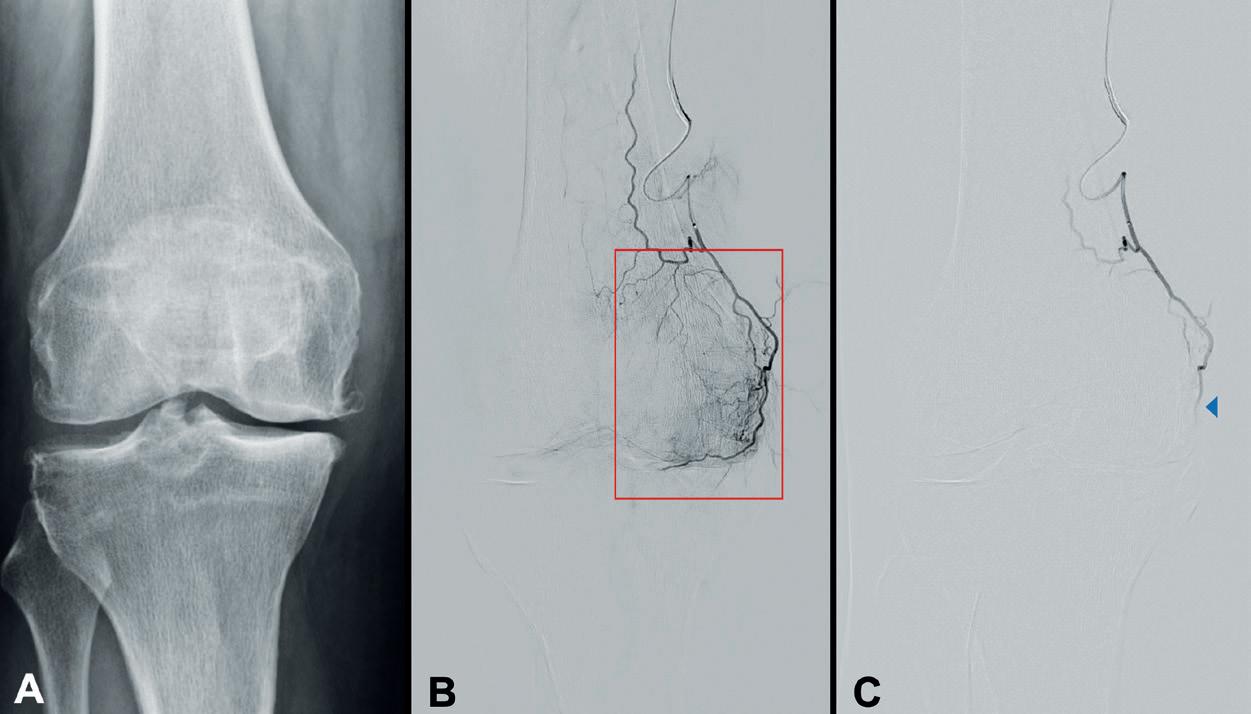

Accumulating long-term IVL data spark debate on key outcome measures for CLTI

Data on peripheral intravascular lithotripsy (IVL) for the treatment of calcified lesions below the knee (BTK) in patients with peripheral arterial disease (PAD) have rapidly emerged in recent weeks. At the 2025 Vascular Interventional Advances (VIVA) conference (2–5 November, Las Vegas, USA), several studies including DISRUPT BTK II, FORWARD PAD, and POWER PAD II delivered positive reports, some contributing to the longest follow-up of patients treated with IVL to date. As industry races to produce data for the newest devices, clinicians speak to Interventional News on the outcomes that matter most as continued assessments determine how IVL fits in the armamentarium of calciummodifying technology.

Several late-breaking data presentations at VIVA 2025, Ehrin Armstrong (Swedish Medical Center, Denver, USA) shared 12-month results from the postmarket, prospective, multicentre DISRUPT BTK II trial, evaluating the Shockwave IVL system (J&J MedTech/Shockwave Medical) in 250 patients with 305 lesions across 38 sites globally.

In the study, 58.5% of patients presented with baseline wounds, 80% with chronic limb-threatening ischaemia (CLTI), 70% with diabetes mellitus, 30% with chronic total occlusions (CTOs) and 85% with moderate-to-severe calcium. The research team demonstrated a 94.8% freedom from major target limb amputation, with no amputations observed among non-CLTI patients. Freedom from clinically driven target lesion revascularisation (CD-TLR) was achieved in 84.5% of patients and Rutherford classification improvement was reported in 75.5% of patients at one-year follow-up.

Among those with CLTI at baseline, 8.1% of patients experienced an amputation. Significant symptomatic and

VascuQoL improvements were also documented, with a more than five-point increase from baseline (11.9±4 to 17.2±5, p<0.001) at one year.

Armstrong noted that the “DISRUPT BTK II study represents a complex, truly real-world patient and lesion cohort,” highlighting high rates of diabetes mellitus, severe target lesion calcification, dialysis-dependent renal failure and CLTI with wounds. He added that the trial has set a “new standard” by introducing IVL as a “frontline strategy” to modify calcification and restore vessel compliance.

Continued from page 1

better to our definitive treatment—be it plain balloon angioplasty, a drug-eluting device or stenting.”

In a CLTI population, von Stempel adds that IVL allows clinicians to “be a little gentler” in vessel preparation, offering a strong safety profile even if the treatment is unlikely to work in the most severe cases. He now uses IVL five to 10 times a week “for everything from iliac disease down to the pedal vessels”, guided by intravascular imaging (IVUS).

For Raghu Lakshminarayan (Hull University Teaching Hospital, Hull, UK), who has been using IVL for approximately five years, the technique’s impact on calcific disease is reflected by the sharp rise in UK utilisation. “Around 5,000 catheters were sold in the UK last year, which is substantial. There’s proven safety and efficacy data and now we’re working to see if it improves amputation-free survival, that’s the bottom line,” he says.

In Europe, however, reimbursement challenges limit access, states Peter Reimer (University Hospital Freiburg, Freiburg, Germany), who adopted IVL after witnessing its successes within clinical trials. “In Germany, you have to justify when and why you want to use a device, discuss it with your hospital administration, present the costs and argue that, by using IVL upfront, you might avoid other expensive interventions such as multiple stents,” he describes. Reimer defines how IVL can also be used off label to soften calcium that has grown outside of a stent and is compressing it before re-dilating rather than placing more stents, creating a costly “full metal jacket”, he says.

Priority outcome measures

As solid justification builds through emerging data, speakers agree that outcome measures must reflect

what is most meaningful to clinicians and patients. Lakshminarayan highlights reintervention rates and amputation-free survival as key endpoints for trials in this arena. Above all, he hopes that a reduction in reintervention rates will “improve patient quality of life and reduce costs”, particularly given how high reintervention rates typically are for calcific disease.

Reimer similarly highlights mobility, explaining that “if they can walk, mortality decreases significantly. But if they undergo major amputation, it’s fatal”. In his view, maintaining ambulation in this patient population is the “most important outcome measure”.

Von Stempel, however, argues that powering a CLTI IVL study to evaluate amputation-free survival is “too narrow” a clinical outcome in this complex group of patients. “If you look at wound healing, if you look at tissue loss—all of these things—I don’t think they are particularly robust outcome measures. We need to develop a win ratio which is a composite measure of outcomes. CLTI is such a minefield to study,” he says.

First-ever IVL CLTI registry

To address this, a first-of-its-kind study has been launched to evaluate the role of IVL in CLTI: the Chronic Limb-Threatening Ischaemia treated with Intravascular Lithotripsy Observational (CALCIO) prospective cohort study—funded by Shockwave Medical in collaboration with the Cardiovascular and Interventional Radiological Society of Europe (CIRSE). The study’s aim is to collect real-world data to better understand clinical effectiveness while avoiding the narrow scope of randomised controlled trials, explains Reimer, a coordinating investigator. The study will assess Shockwave Medical’s IVL system in promoting wound healing and preventing amputation in CLTI patients with calcified femoropopliteal or crural lesions. The primary outcome is a composite of wound healing and freedom from amputation of the treated limb at 12 months. Secondary objectives include wound healing at 24 months, freedom from amputation at 24 months, and amputation-free survival and primary and secondary patency rates at 12 and 24 months.

Raman Uberoi (John Radcliffe Hospital, Oxford, UK), co-chief investigator for CALCIO alongside Reimer and Christoph Binkert (Kantonsspital, Winterthur, Switzerland), told Interventional News that

the goal is “not to change what clinicians are doing, but to collect real-world data on how people are using IVL and outcomes”. Recruitment is currently ahead of schedule, and he hopes that “by this time next year, we will be analysing preliminary data”.

“We hope CALCIO provides more resonance and impact for users, potential users and regulators,” Uberoi says, adding that industry trials will continue to deliver “important basic data on device function. This will be crucial to provide vital data needed by regulators to accept IVL in the treatment of CLTI to gain funding”. He notes that it will be interesting to see whether differences emerge between newer devices entering the market, which he currently believes are largely similar. Ultimately, he says, the boom in IVL research and manufacturing reflects companies “cashing in on a pretty safe bet” as evidence for the technique’s efficacy continues to grow.

A bid for more pulses

Looking to the future, von Stempel believes that dual assessment of IVL through industry-led data and proceduralist-driven studies “will really disrupt the way we assess outcomes” over the next five to ten years. As IVUS and IVL become “cheaper and more ubiquitous”, he adds, outcomes will be measured more objectively.

For now, however, Lakshminarayan notes that cost and access remain challenges. While IVL may reduce reintervention—and therefore overall cost— technological limitations persist, particularly regarding pulse capacity and balloon sizing. The 300-pulse limit of the IVL catheter is inadequate in his experience, and Uberoi adds that it is “cynically, a means to sell more devices”, questioning: “If the balloon is intact and shocking, why stop at 300 pulses?”

Where there is smoke, there is fire, Lakshminarayan suggests: the increasing industry attention surrounding IVL must indicate its effectiveness. “If approximately 34 industry partners are currently bringing IVL devices to market, this must mean, as a technology, it works well—otherwise, why would so many invest in it?” He concludes that growing discussion around cost, availability and clinical value will determine whether the technology “is truly worth it”, as interventionists wait to see whether its potential will be confirmed by upcoming trial data.